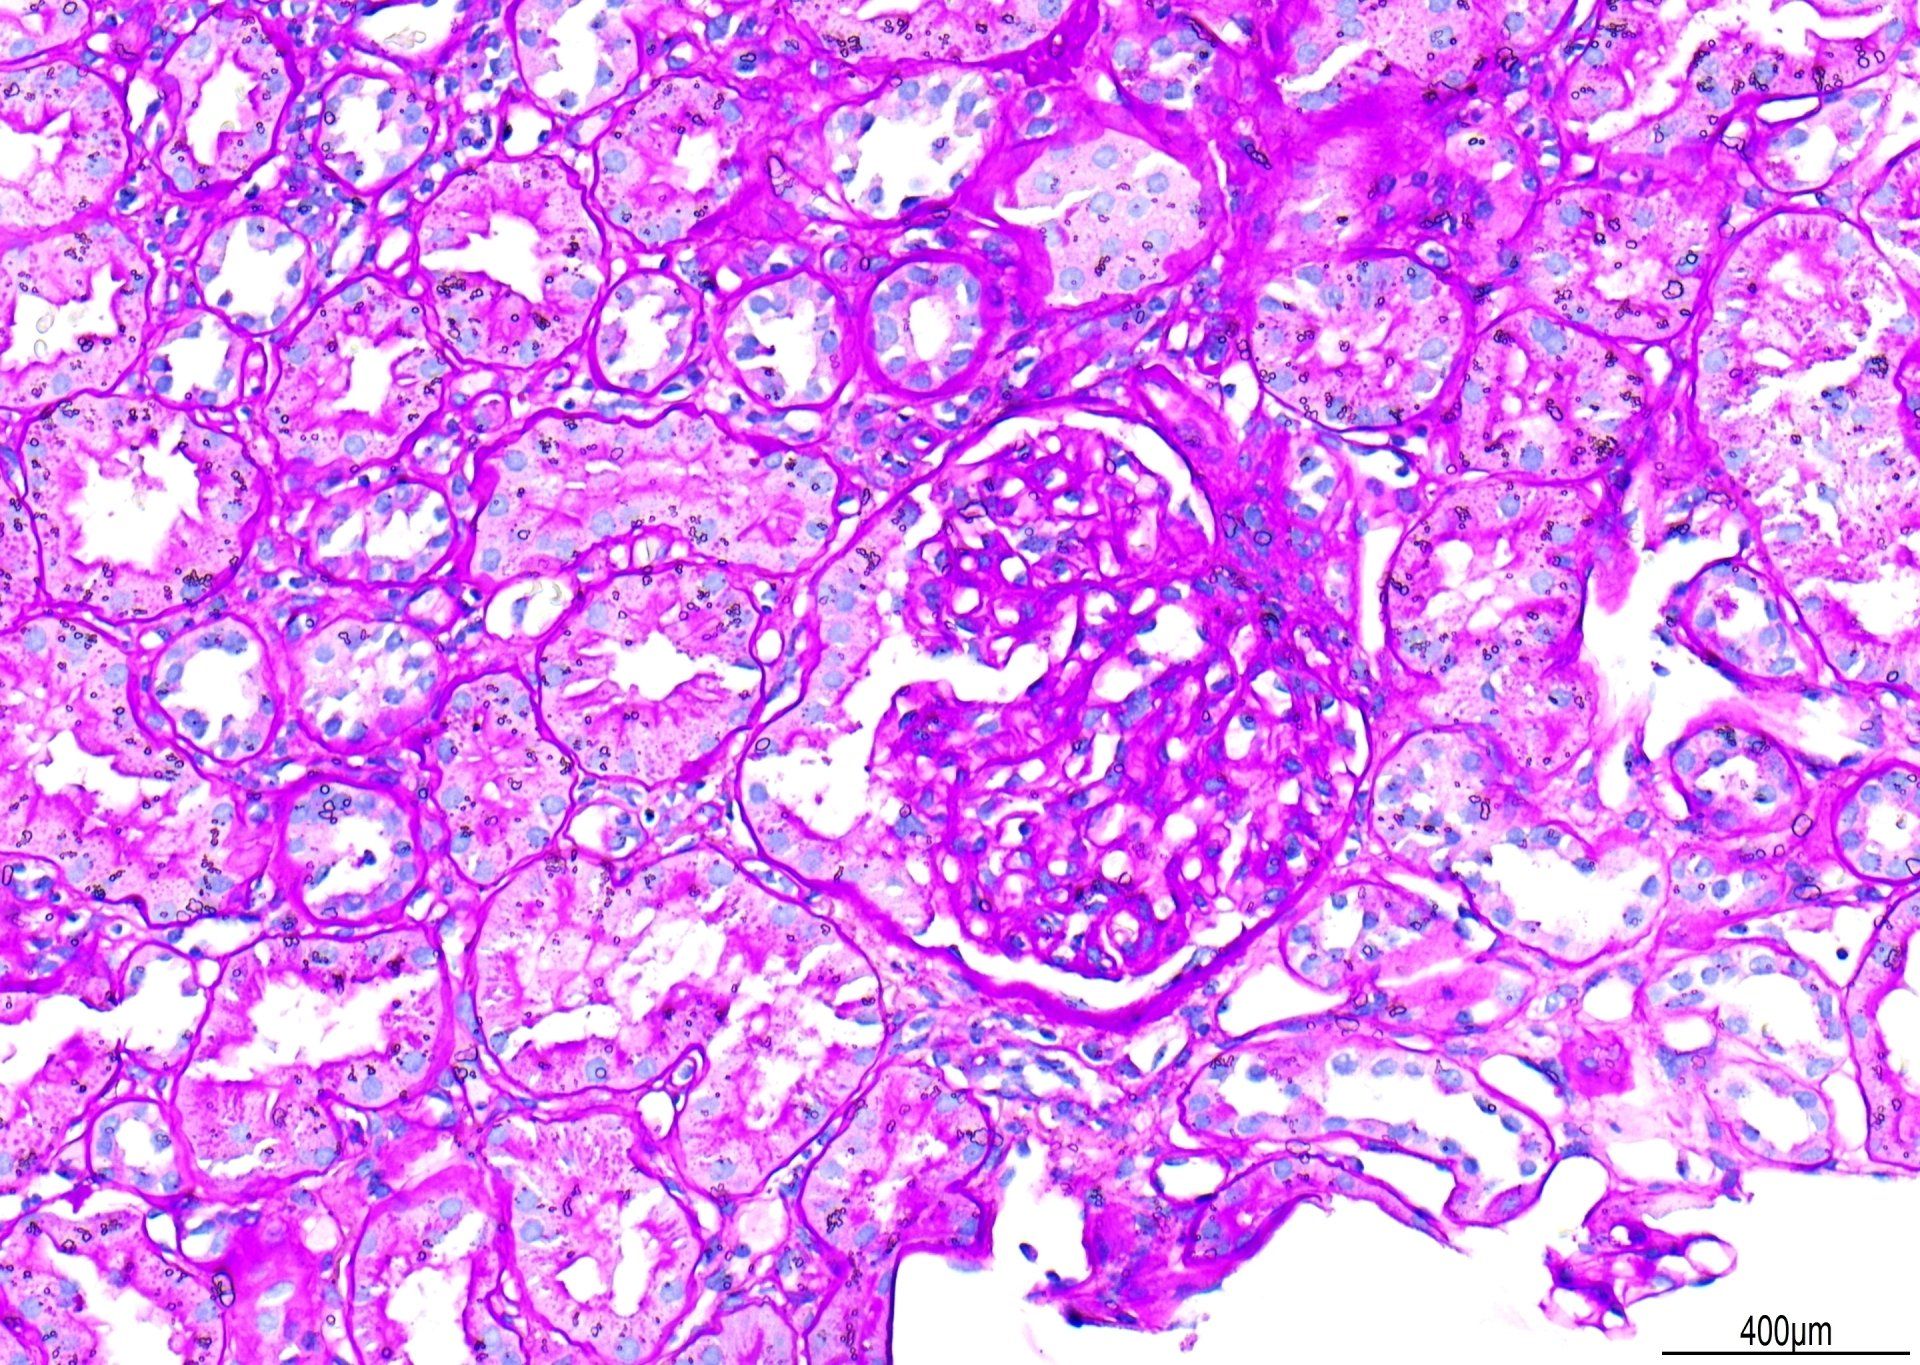

PAS - Renal Scheme

Nakita sa x20, ito ay isang halimbawa ng PAS stain. Ibinawas ang mga marka para sa 'primary background staining.' Bagama't ang mga glomerular basement membrane ay mahusay na nabahiran, ang kaibahan ay maaaring maging mas mahusay kung mayroong mas kaunting background Schiff staining. Bilang karagdagan, ang mga patak ng tubig ay nakita sa ilalim ng coverslip. Ang kabuuang marka para sa seksyong ito ay nakakuha ng 7/10.